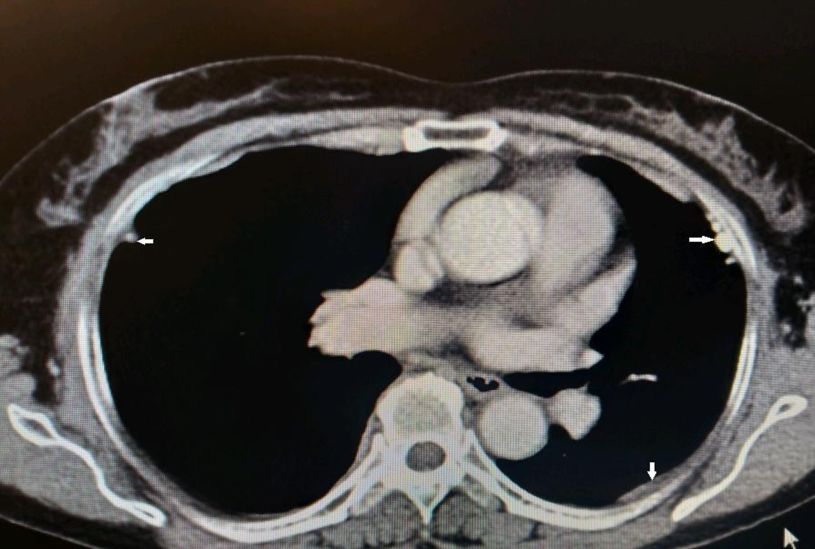

图示:患者两侧胸膜可见结节、钙化影(白箭)

到目前为止,除了胸腔积液之外,仔细阅读该患者胸部CT发现该患者的另外一个特点就是胸膜增厚、结节、钙化影。通过这一线索,不排除有胸膜来源疾病的可能。

影像学主要表现为胸腔积液、胸膜肿块和胸膜增厚。典型的表现为胸内弥漫性不规则胸膜增厚和突向胸膜腔内的驼峰样多发结节,呈波浪状阴影,在胸液引流后行X线检查可能发现肺部网状阴影、胸膜斑等石棉接触的证据。